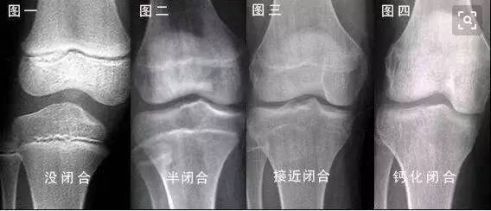

检查结果发现小华的骨头和骨线的发育已经闭合,孩子想要再长个,其实很困难,其实不仅是王姐,很多父母都和她有同样的想法。觉得每天吃好喝好,孩子的营养充足,可能是晚长而已,不用太着急,但是事实上并不是所有的孩子都会这样,如果错过了孩子长高的黄金期,骨骼线闭合后,孩子的身高基本上就定型了。

医生说:“现在孩子发育比较都比较早,一般正常男孩的骨骼线闭合时间在13岁至16岁之间。如果孩子到了这年纪身高还没有170,过了这个岁数以后,可能以后再难长个了,当然不排除有些孩子长得晚,但是这些是概率问题,父母要多重视。